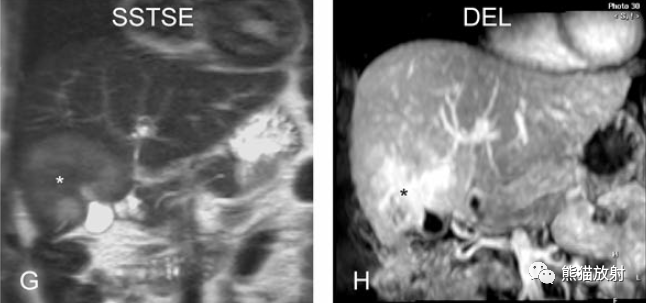

膽囊癌。病灶以膽囊為中心侵及肝臟,明顯彌散受限,由于病灶內含結締組織/纖維成分(T2低信號)導致肝被膜內陷,增強掃描動脈期明顯不均質強化,延遲期中心纖維成分延遲強化。表現類似肝內膽管細胞癌。